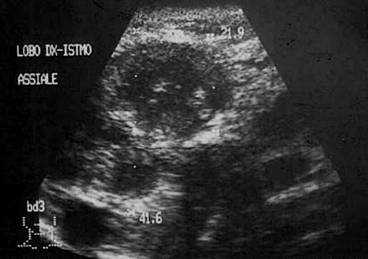

Lob stang, proiectie trasversala si longitudinala

Barbat de 55 ani. Formatiune nodulara voluminoasa ce ocupa 2/3 din lobul stang, hipoecogena, neomogenea, de 20 x 23 x 44mm(10 cc). Citoaspirata ecoghidata: carcinom midolar. Confirmat histologic.

Scintigrafia si CT aceluiasi pacient, metastaza laterocervicala stg ce impinge traheea spre dr.